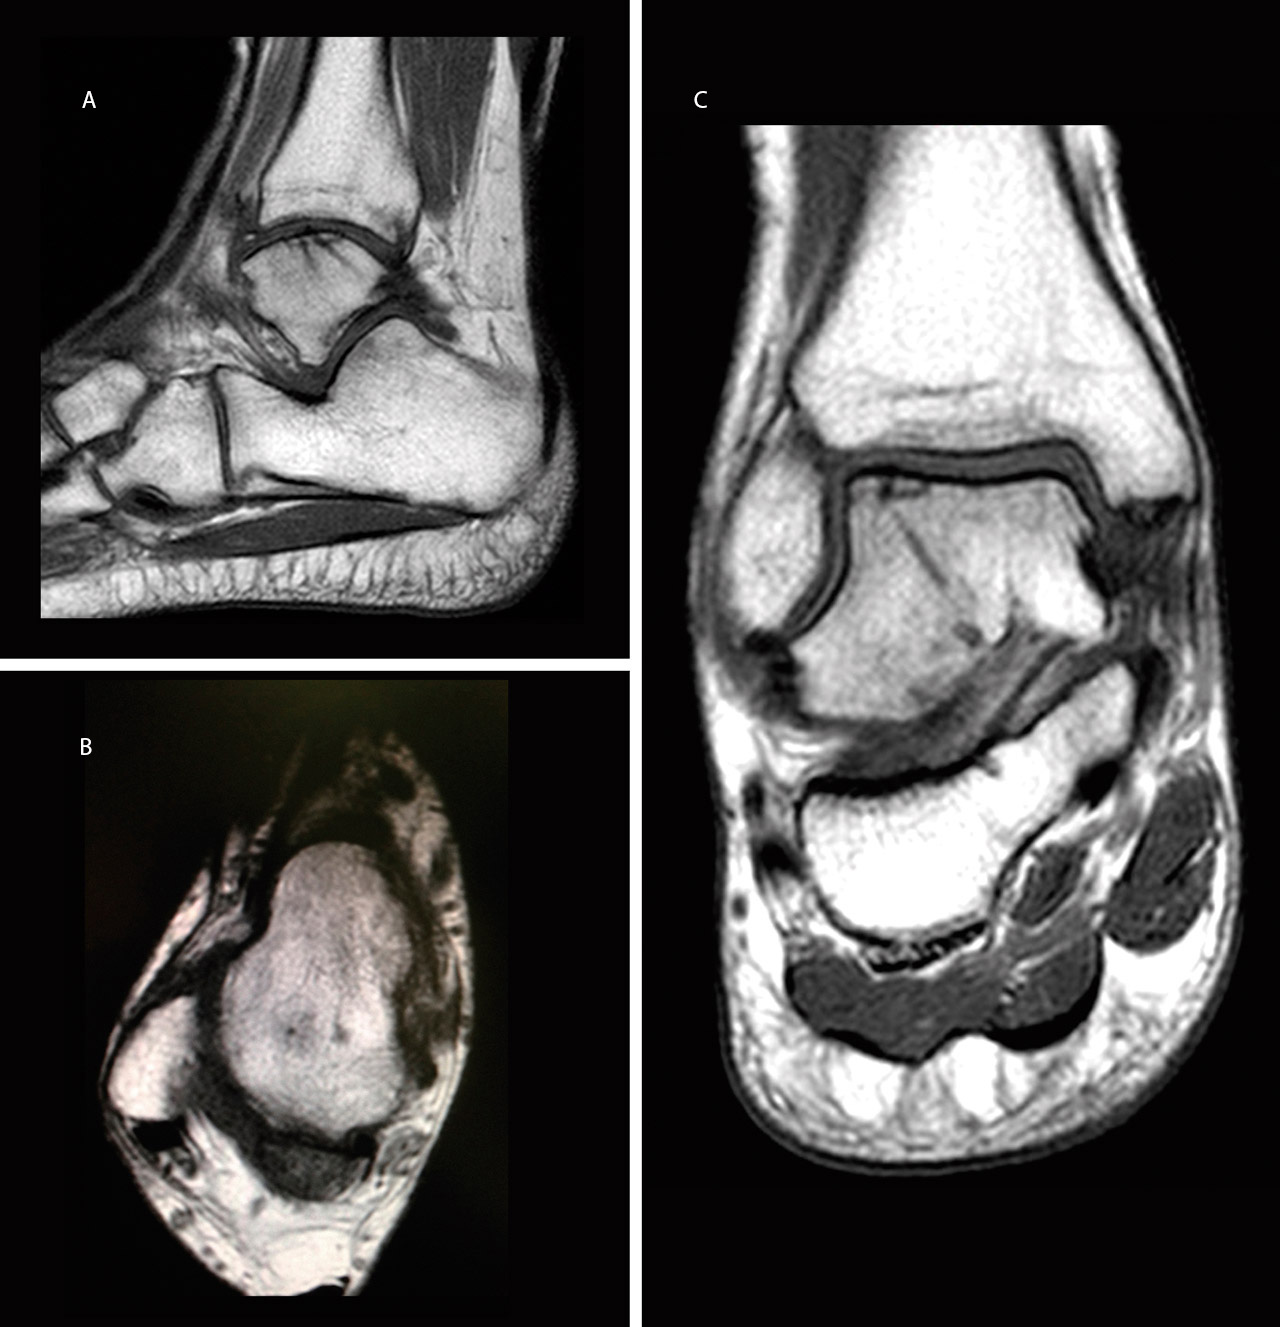

Se trata de un varón de 22 años de edad, atendido en urgencias por dolor en tobillo derecho tras mecanismo de supinación e inversión forzada en el tobillo derecho. Fue diagnosticado inicialmente de esguince de tobillo de grado II-III e inmovilizado con una férula suropédica durante 3 semanas. Inicialmente no se realizó ninguna prueba complementaria debido a que el paciente no cumplía los criterios de Ottawa. Cuando inició la deambulación, debido a la persistencia de dolor, tumefacción y limitación en la flexión dorsal del tobillo, a las 4 semanas se realizó una radiografía (Rx) en la que se observó un defecto óseo compatible con una LOT en la cúpula astragalina anteroexterna del tobillo (Figuras 1A y 1B). A los 5 días se realizó una tomografía computarizada (TC) que mostró una fractura osteocondral con fragmento de 1 cm2 volteado 180° (cartílago articular en contacto con hueso subcondral del talus), en la zona 3 de Elias(5)(Figuras 1C y 1D), por lo que se decidió realizar tratamiento quirúrgico.

El paciente se reincorporó a su actividad laboral (mozo de almacén) y deportiva a los 4 meses del accidente, sin dolor ni inestabilidad y con un rango de movilidad completo del tobillo. A los 6 meses se realizó una resonancia magnética (RM) que mostró la integración del fragmento, sin escalón articular ni signos de inestabilidad (Figura 3).